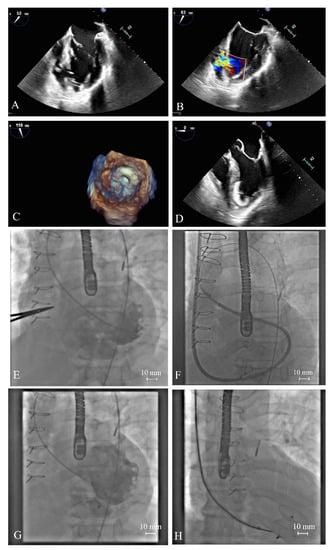

- Molek, P.; Wlodarczyk, A.; Gajos, G.; Nessler, J.; Zalewski, J. Simultaneous cardiac free wall rupture and ventricular septal rupture following acute myocardial infarction treated with emergency balloon closure. Pol. Arch. Intern. Med. 2019, 129, 830–832. [Google Scholar] [CrossRef]